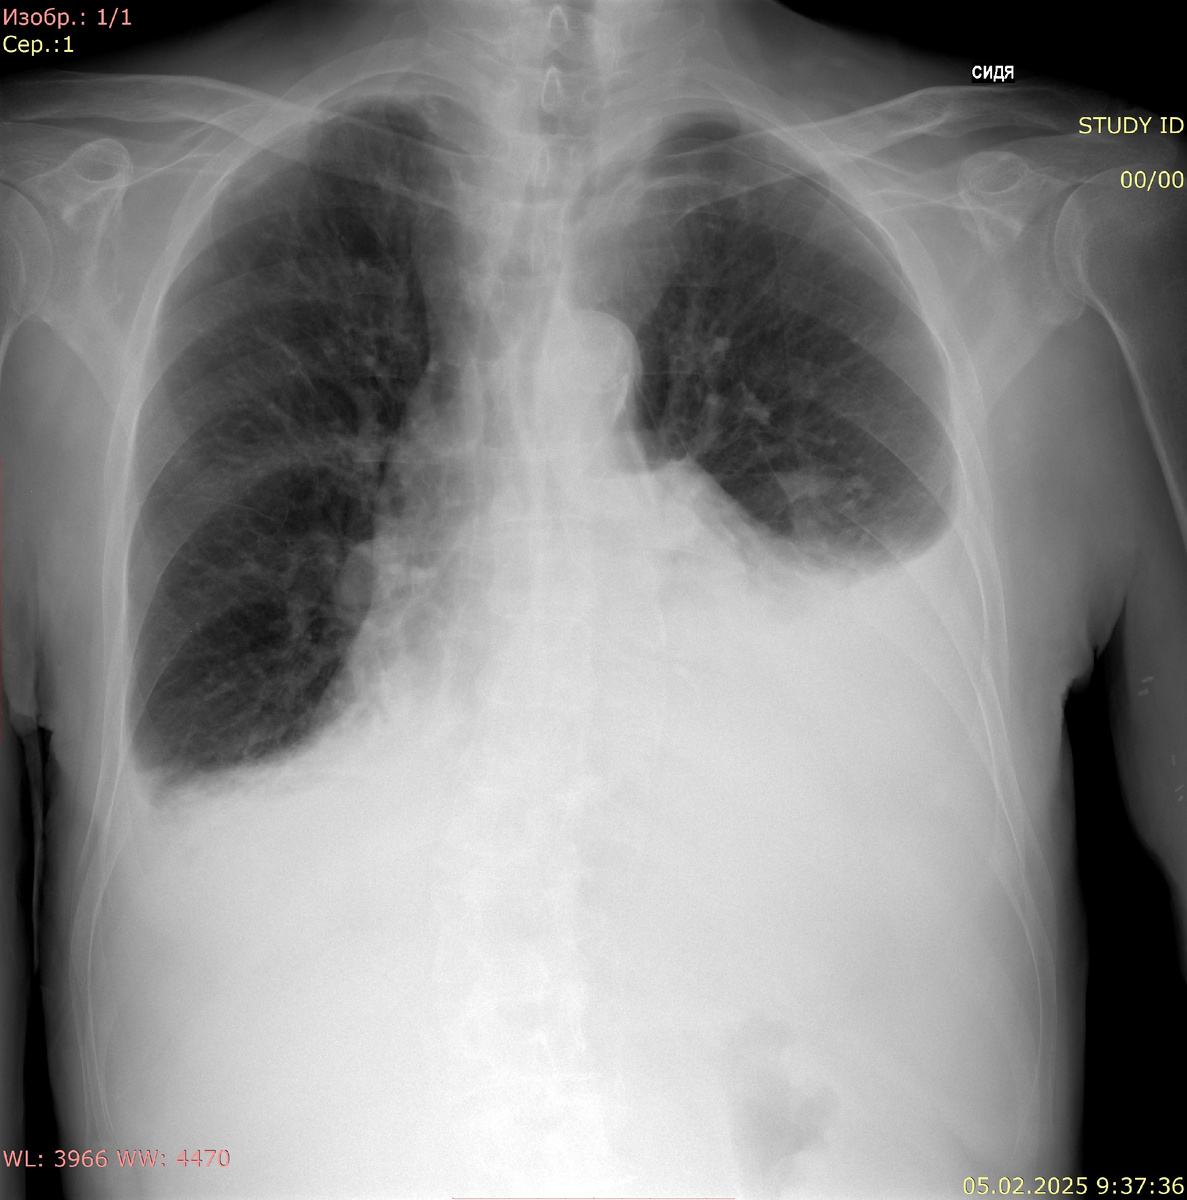

Рентгенография органов грудной клетки в прямой проекции, сидя Протокол:

Тень средостения не смещена, не расширена. Корни структурны, не расширены.  В легочных полях тени плеврального выпота (слева до 4-5 ребра, справа до 6-7 ребра). Свободного газа нет. Контуры диафрагмы четкие, ровные. Костно-деструктивных изменений не выявлено Заключение: Двусторонний плевральный выпот Рентгенография органов грудной клетки в прямой проекции:

Рентгенография органов грудной клетки в прямой проекции, сидя

Протокол:

Тень средостения не смещена, не расширена. Корни структурны, не расширены.  В легочных полях тени плеврального выпота (слева до 4-5 ребра, справа до 6-7 ребра). Свободного газа нет. Контуры диафрагмы четкие, ровные. Костно-деструктивных изменений не выявлено

Заключение: Двусторонний плевральный выпот